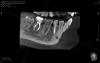

red_butler Опубликовано 23 апреля, 2013 Поделиться Опубликовано 23 апреля, 2013 Собственно проблема с 4.7 выявлена перед ортодонтией, пациентку ничего не беспокоит, изредка слабый лимфоаденит. Посмотрели с эндодонтистом, склоняемся убрать и пациентка хочет того же. Вопрос следующий прогноз при ретрите и когда после пломбирования ставить систему на низ. Ссылка на комментарий

Afffinity Опубликовано 23 апреля, 2013 Поделиться Опубликовано 23 апреля, 2013 А я за удаление и костную пластику. С таким разрежением ,имхо, этот вариант наиболее прогнозируемый. Ссылка на комментарий